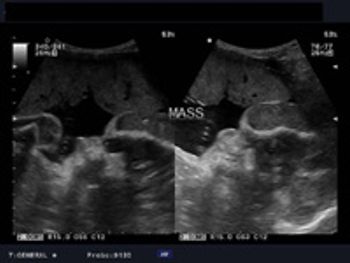

Several recent studies have shown that the addition of secondary ultrasound markers to the combined first-trimester screening for aneuploidies, or chromosomal abnormalities such as trisomy 21 (Down syndrome) and trisomy 18 (Edwards syndrome), can slightly improve screening accuracy.